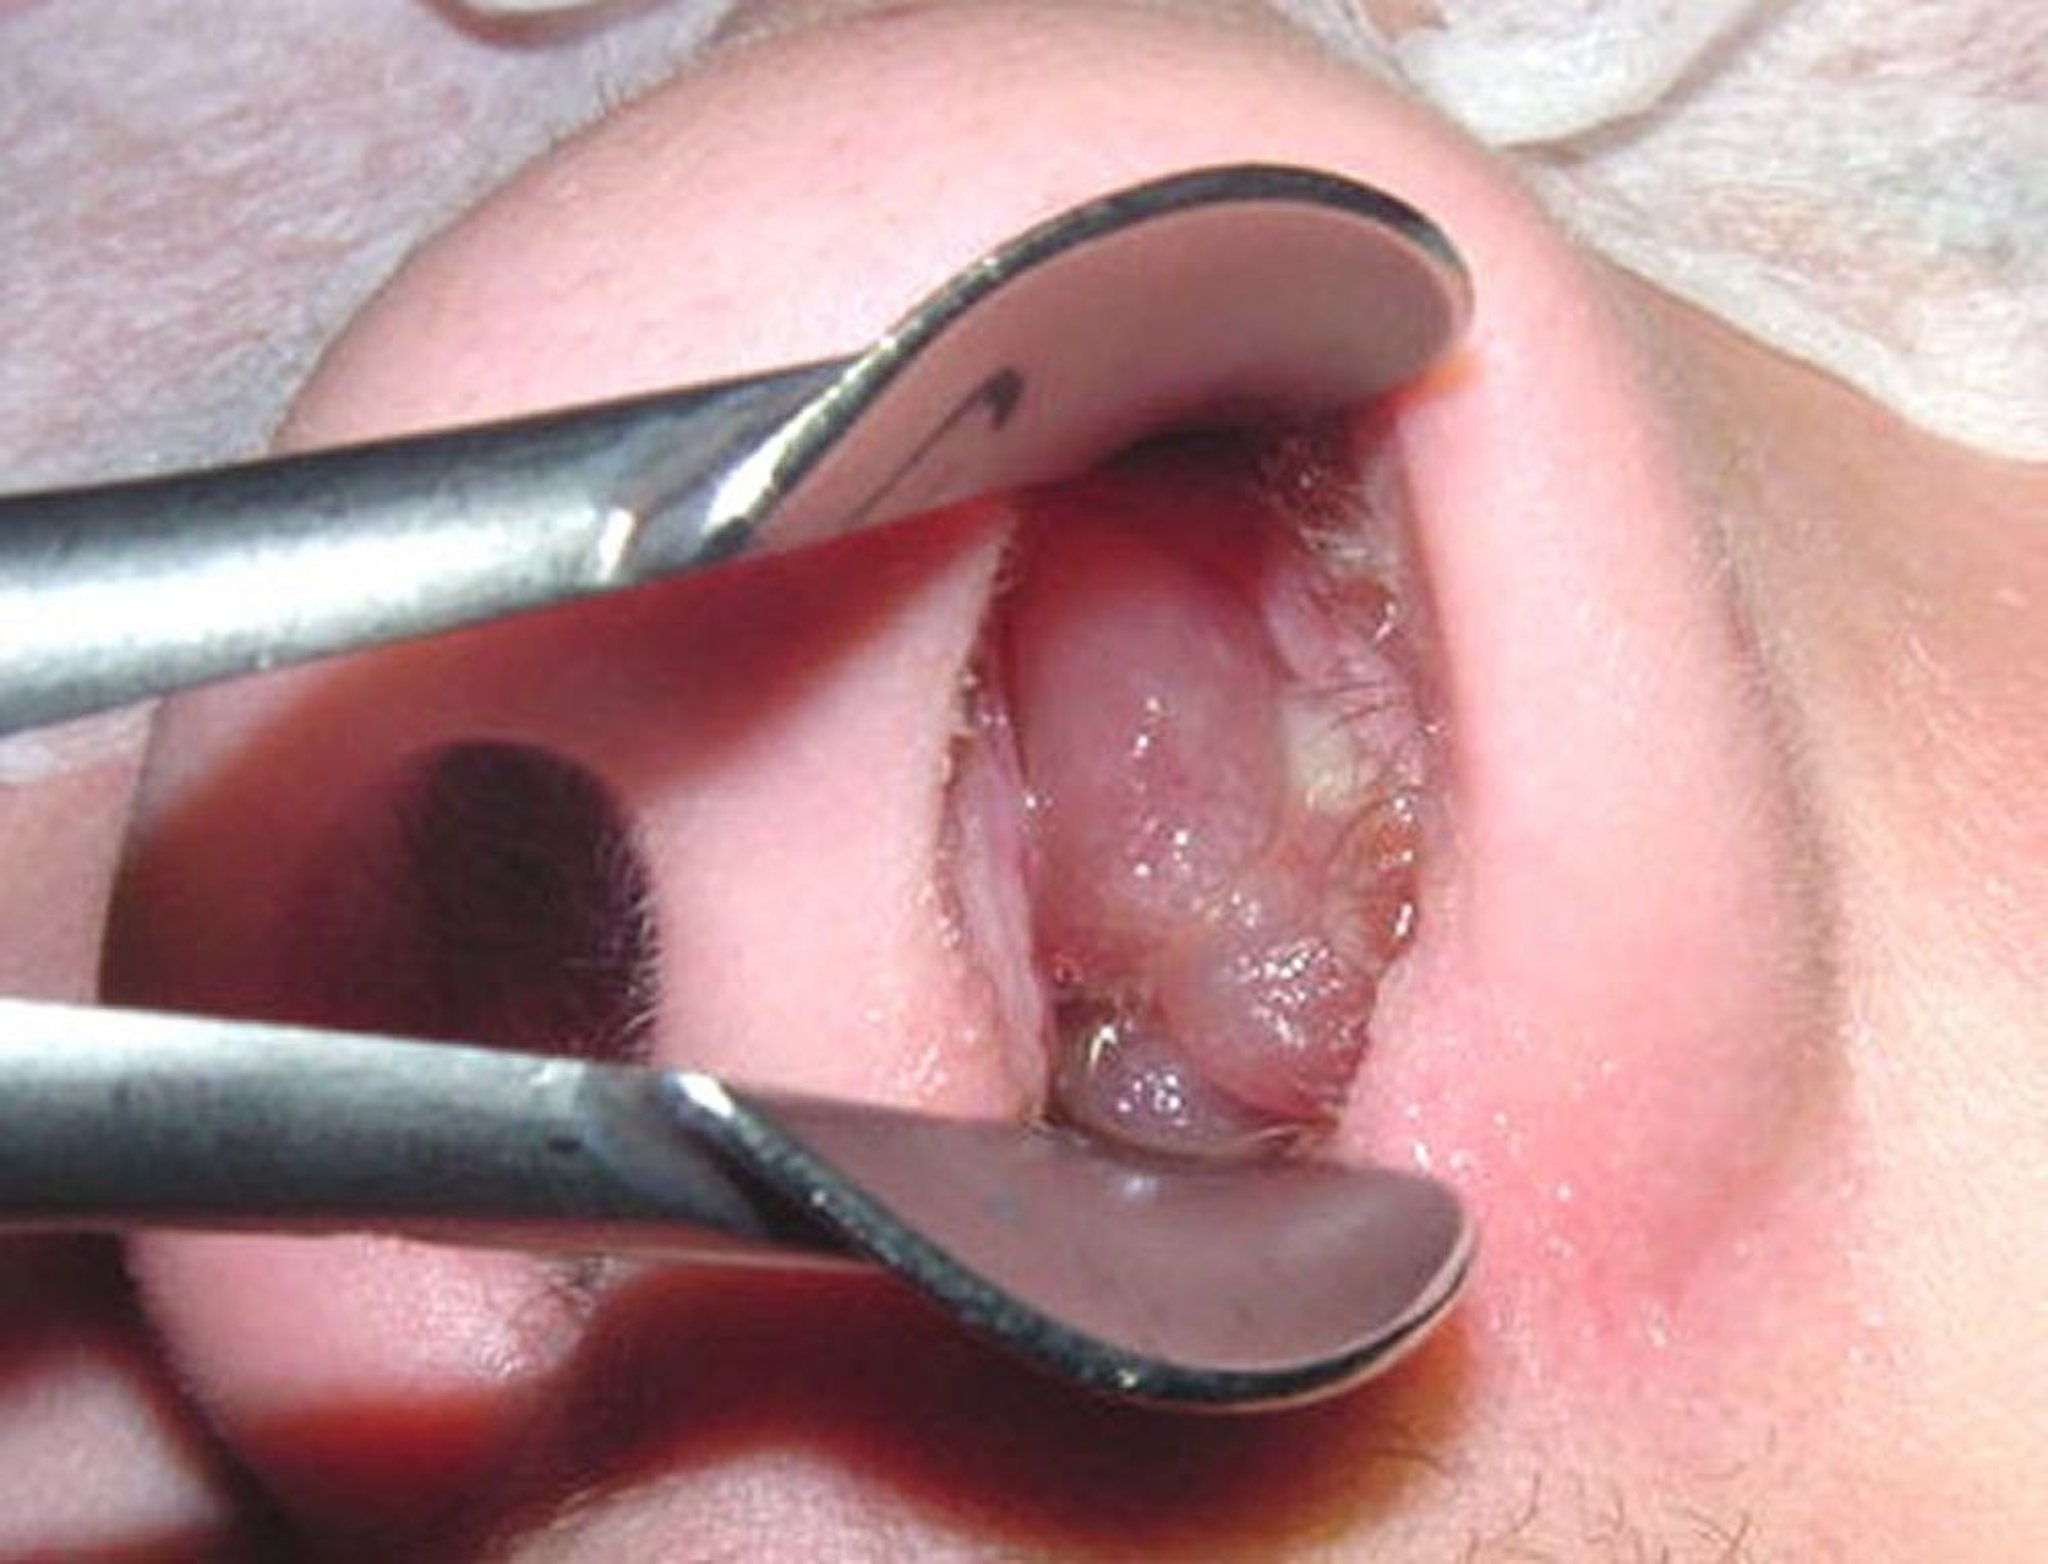

Um pólipo nasal maduro pode lembrar uma uva descascada sem sementes.

Image provided by Bechara Ghorayeb, MD.